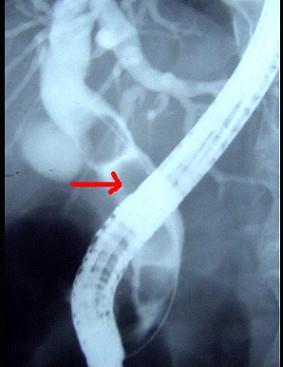

下列ERCP检查最佳的诊断是 ( )A、肝内外胆管结石B、胆囊息肉C、胆总管结石D、肝内胆管结石E、胆囊结石

问题 下列ERCP检查最佳的诊断是 ( )

选项 A、肝内外胆管结石 B、胆囊息肉 C、胆总管结石 D、肝内胆管结石 E、胆囊结石

答案 C